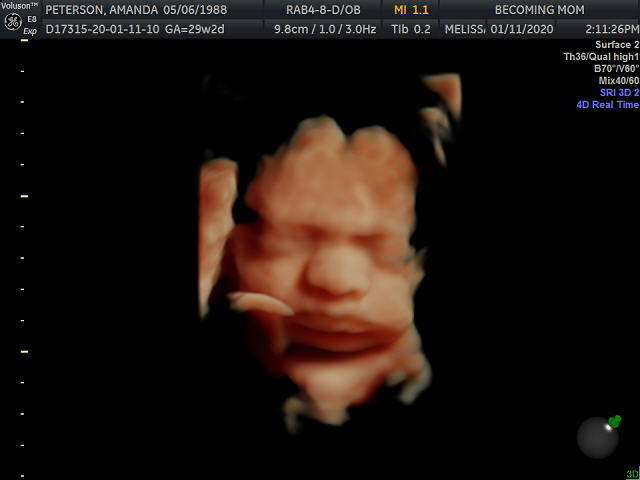

Hands down, the best part of this week was getting to see our baby girl via 3D/4D Ultrasound! Justin bought me a session at Becoming Mom as a Christmas gift, so he, my mom and I went on Saturday to see our sweet girl.

In addition to the unicorn, we got 26 photos and a video as a result of our visit (which I promptly forwarded on to all our family members and a few friends!). Her hand and her knee were up by her face the entire time, and the technician kept poking my belly to get her to move them. She would oblige, for two seconds, and then bring them right back up. Stubborn girl!

I am so obsessed with her little squishy nose and those cheeks!!! I can hardly believe that this precious face is a product of Justin and me. Reproduction is incredible. She’s so perfect, and now I’m even more anxious to meet her.

My first reaction was – “Where in the heck did she get those cheeks? Neither one of us had those cheeks as a kid!” Then my Aunt sent me this photo of me…

Turns out I had some cheeks too. Perhaps she looks like mama after all? 🙂 What do you think?!